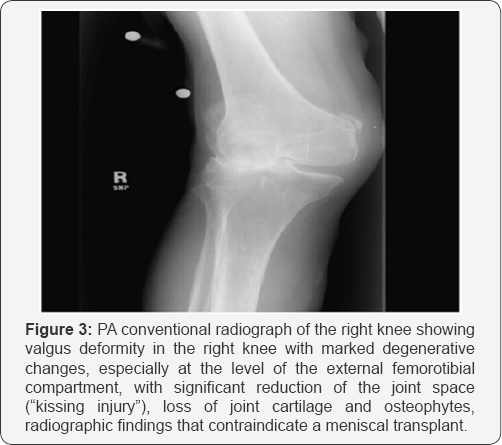

e. Changes grade III-IV of Fairbank in tibia and femur (lesions "in kiss") (Figure 3).